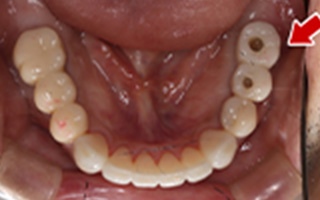

Before

After

| 60歳 男性 | 歯科大学病院 教授からの紹介 ご本人は産婦人科医 |

|---|---|

| 主訴 | 左下に歯が無くて食事がしずらい |

| 処置内容 | 2本インプラント埋入+再生処置 |

| 治療費用 | 下顎: 約80万円(税込) |

| 治療期間 | 下顎: 6ヶ月 |

| リスク | 術後の腫れ、痛み(ピークは3日後、1週間で軽減) |